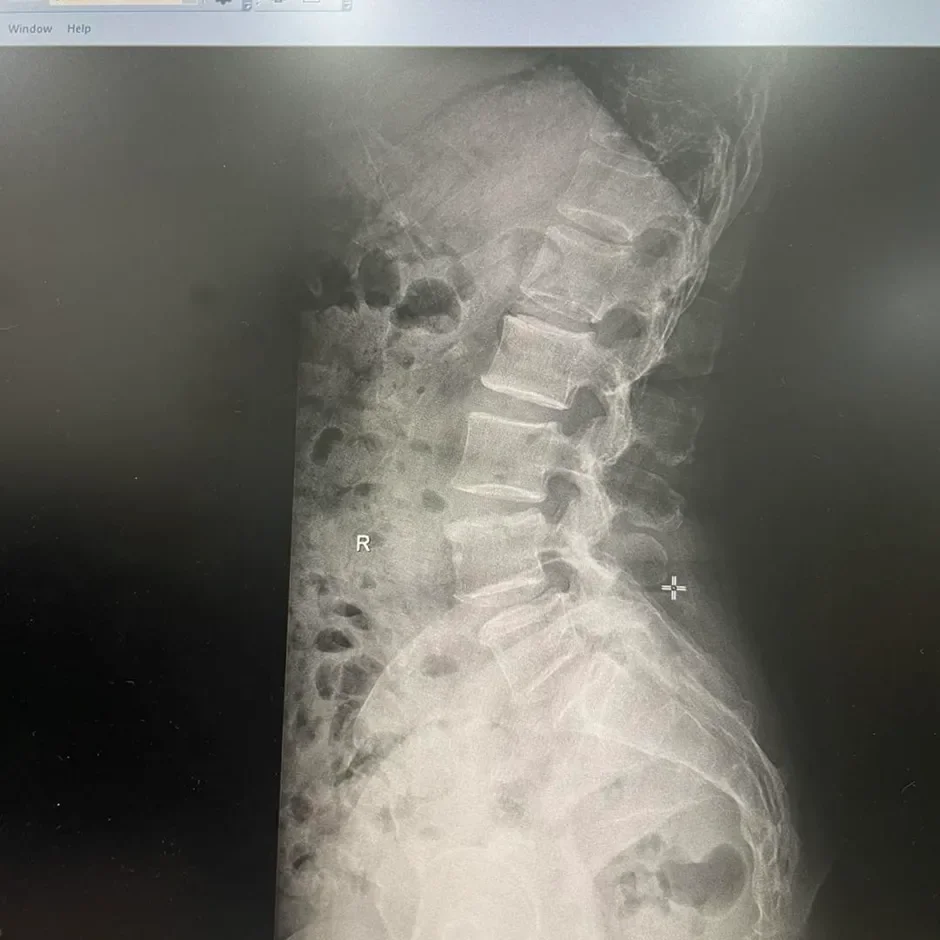

△ 初步体检:膝关节轻度肿胀和部分畸形。膝关节X线片显示早期骨关节炎。

④ 腰椎X线片显示:L4-L5和L5-S1椎间隙变窄;L5椎体I度前滑脱。这与患者背部放射至腿部的疼痛症状相符。因此,诊断为腰椎间盘突出伴神经根受压。